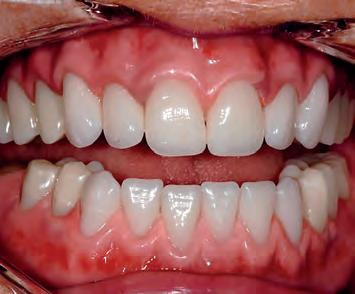

Matt Everatt I EditorPlanned restoration: The patient required a fi xed implant-supported restoration for the upper and lower jaw

Workflow:

- Impression taking and bite registration with existing prostheses; 3D face scans with Face Hunter

-Tooth set-up, digital design in Zirkonzahn.Modifi er to correct occlusion and aesthetics, and fabrication of new prostheses made of Temp Basic resin

-Implant planning and production of surgical guides with Zirkonzahn.Implant-Planner

-Printing the implant models according to the implant planning, with integrated laboratory analogues

-Integration of pins to stabilise the surgical guides the immediate temporaries, ensuring a correct 3D orientation; printing of surgical guides and temporaries

-Implant placement and impression taking after the healing period

-Design and milling of the fi nal restorations in Prettau ® 2 Dispersive ® zirconia